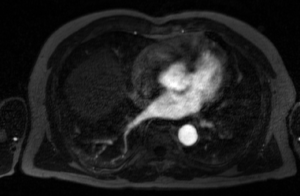

MRA Image Immediately Post-ablation LGE-MRI Image CT Image

Carma ex mra.png

Carma no reflow.png

• MRAs have a bright blood pool, the bounds of which indicate the endocardial surface of the LA wall.

• Immediately-post ablation scans exhibit large, bright areas in and around the LA walls, reflecting edema and shape changes caused by the ablation procedures.